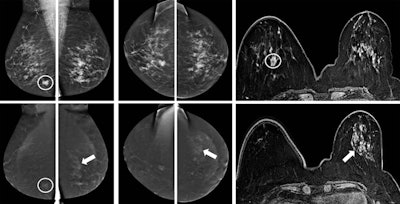

CESM, or contrast-enhanced dual-energy mammography (CEDM), is a mammographic technique in which an iodine-based contrast agent is administered intravenously two minutes prior to image acquisition. In general, an iodine contrast concentration higher than 300 mg/mL is used, with a dose of 1.5 mL/kg body weight. The patient is positioned in the mammography unit like a regular full-field digital mammography (FFDM) examination, with image acquisition consisting of two views per breast: mediolateral oblique and craniocaudal. The procedure uses a low-energy image, similar to FFDM, but it also acquires a high-energy image to visualize iodine uptake.

CESM is generally used in diagnostic settings with clinical indications similar to breast MRI. However, while both CESM and MRI are based on analysis of wash-in and wash-out of breast lesions, several technical differences may influence clinical performance and images interpretation, noted Dr. Clarisse Dromain, PhD, from the imaging department at Lausanne University Hospital in Switzerland, a speaker at Saturday's session. The major differences include 2D versus 3D images, contrast and temporal resolution, type and quantity of contrast agent, acquisition under compression versus free of compression, and positioning, she said.

CESM matches the performance of breast MRI, not only in terms of breast cancer detection, but also in the assessment of disease extent, explained Dr. Marc Lobbes, from the radiology department at Maastricht University Medical Center in the Netherlands. A large, prospective multicenter study conducted wi 178 patients found overall sensitivity of MRI was better than CESM (76% versus 72%), but overall specificity of CESM was better than MRI (94% versus 88%). Furthermore, CESM has fewer false positives than breast MRI, which several studies have confirmed.